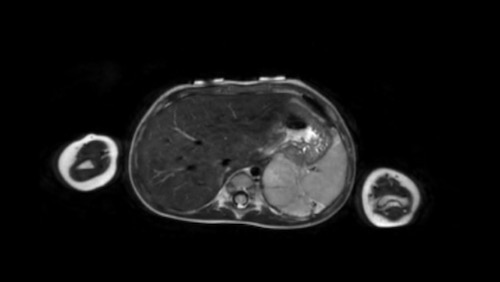

Hình ảnh

Hình ảnh MRI của một bé gái chín tháng tuổi có khối u ở bụng trái. MRI cho thấy khối u tuyến thượng thận trái, một phần đặc, một phần nang. Có nhiều di căn gan.

Khối u đã được sinh thiết. Có tình trạng chảy máu liên tục qua kim dẫn đường. Vào cuối thủ thuật, hai nút bọt gelatin đã được đặt vào (các dải tăng âm (mũi tên)).